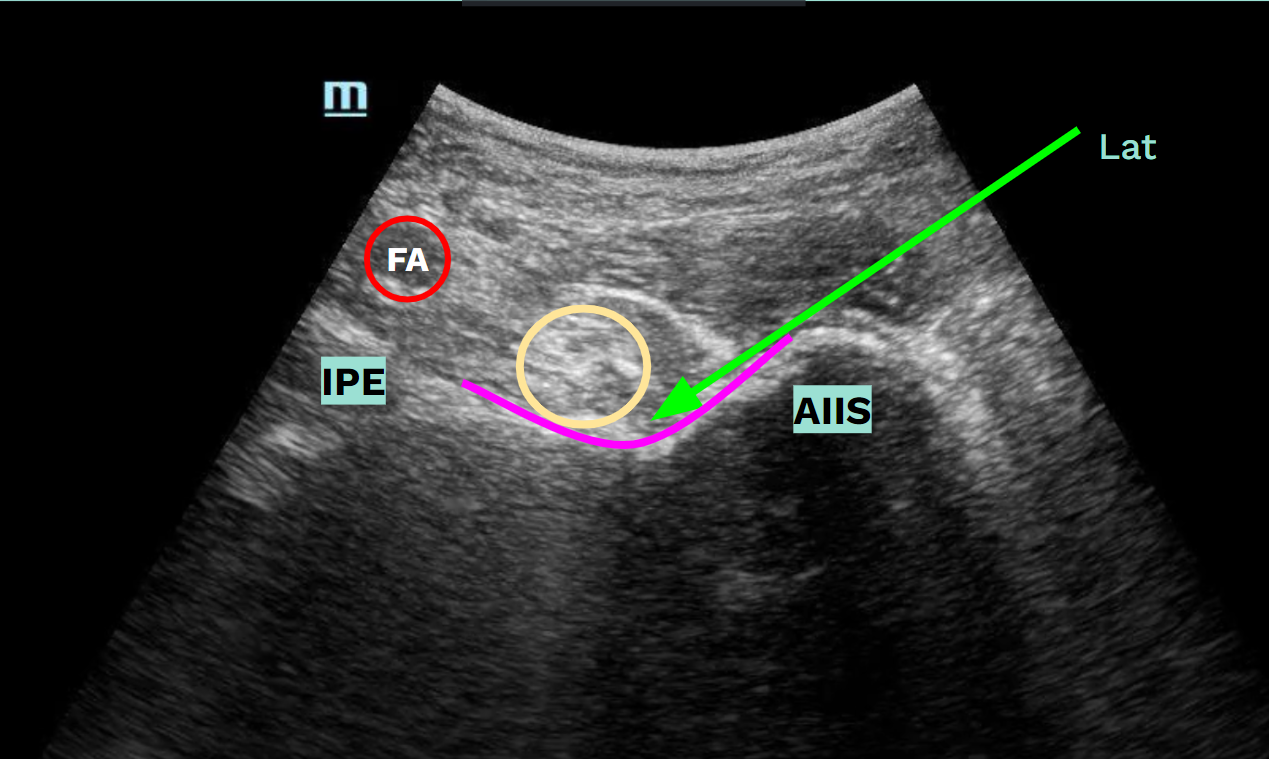

The Pericapsular Nerve Group Block (PENG block) is a novel approach to provide analgesia to the hip joint without affecting the motor function of the quadriceps muscle or altering the sensory exam.